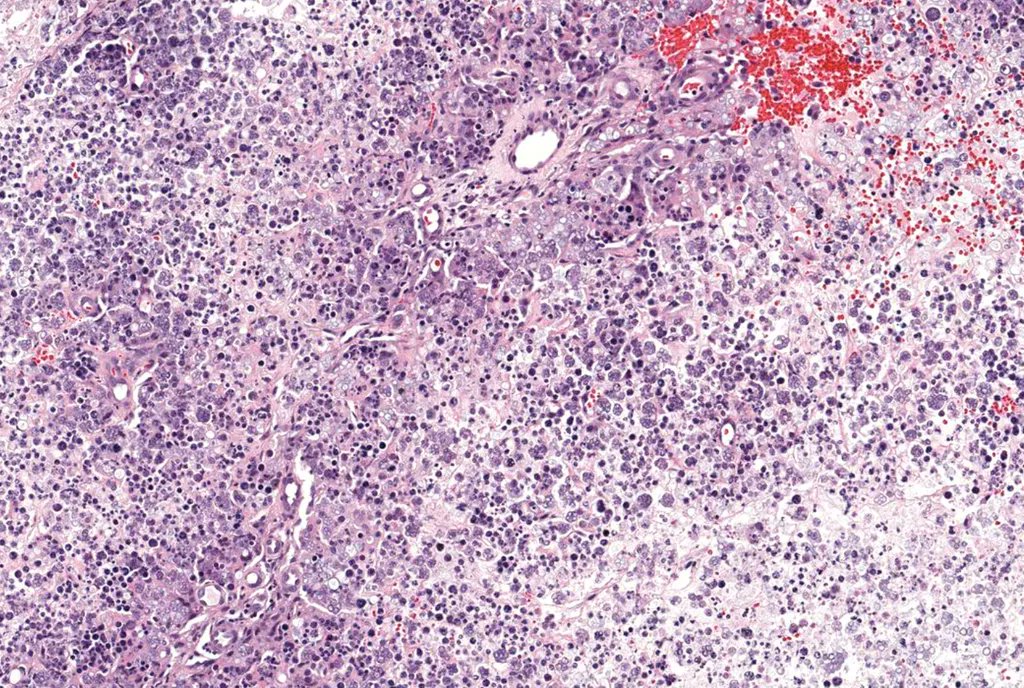

A male in his 20s, presented with a rapidly enlarging painless right scrotal mass. Contributors: Crystal (Yitong) Xu, Kiril_T_Can The GU Pathology Society (GUPS) Case of the Week: gupathsociety.org/COW-2022-16 Send your cases to @akgulMD #GUPSCOW #GUpath #pathology

A male in his 20s, presented with a rapidly enlarging painless right scrotal mass.